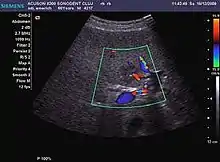

It is the most common liver tumor with a prevalence of 0.4 – 7.4%. It is generally asymptomatic but also can be associated with pain complaints or cytopenia and/or anemia when it is very bulky. It is unique or paucilocular. It can be associated with other types of benign liver tumors. Characteristic 2D ultrasound appearance is that of a very well defined lesion, with sizes of 2–3 cm or less, showing increased echogenity and, when located in contact with the diaphragm, a "mirror image" phenomenon can be seen. When palpating the liver with the transducer the hemangioma is compressible sending reverberations backwards. Doppler exploration reveals no circulatory signal due to very slow flow speed. CEUS investigation has real diagnosis value due to the typical behavior of progressive CA enhancement of the tumor from the periphery towards the center. The enhancement is slow, during several minutes, depending on the size of hemangioma and on the presence (or absence) of internal thrombosis. During late (sinusoidal) phase, if totally "filled" with CA, hemangioma appears isoechoic to the liver. Deviations from the above described behavior can occur in arterialized hemangiomas or those containing arterio-venous shunts. In these cases, differentiation from a malignant tumor is difficult and requires other imaging procedures, follow up and measurements of the tumor at short time intervals.[1]